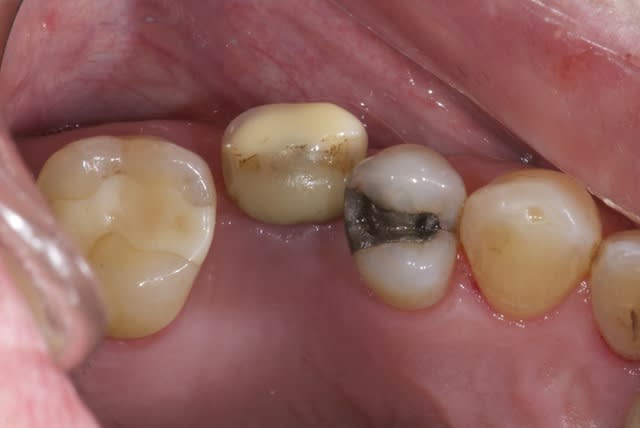

Patient de 33 ans venant pour une molaire douloureuse...

Je pense tenir le record du n'importe quoi implantaire.

Ce qui me dérange le plus, c'est l'age du patient...33 ans et autant de soins....

Ensuite, la super maitrise des soins...même si les implants ont 10 ans, c'est vraiment honteux.